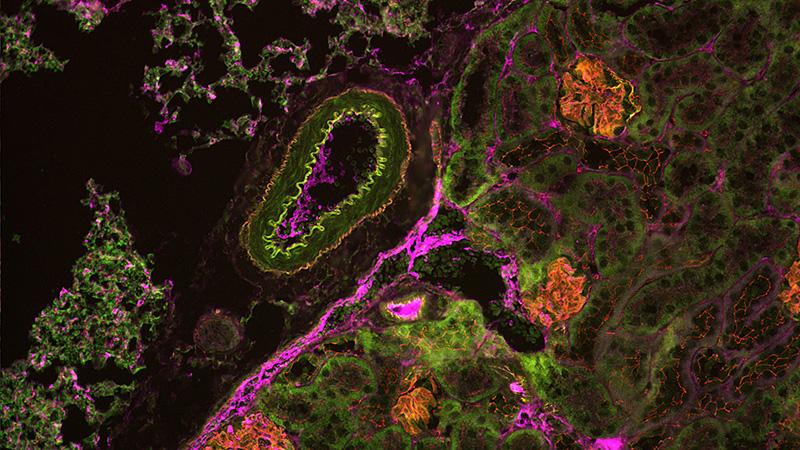

In studies from Schindler et al. (2023) at the University of Medicine Greifswald, the NTR/MTZ system was used to induce FSGS lesions and screen a library of epigenetic modulators and FDA-approved drugs to assess their impact on zebrafish kidneys.8,9 The automated analysis of thousands of zebrafish larval images required substantial storage and processing, which was achieved using Acquifer HIVE. Custom Fiji and image analysis macros enabled vasculature segmentation and the detection of podocytes via mCherry fluorescence.This high-content screening identified Belinostat as protective in an FSGS-like zebrafish model.